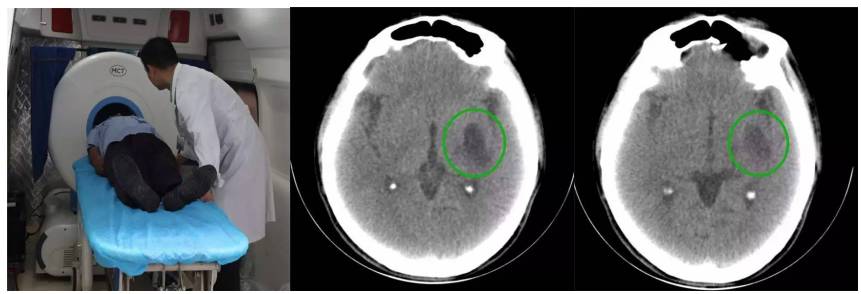

救护车载移动CT陈旧性脑梗塞扫描

救护车载移动CT扫描脑出血后软化灶形成